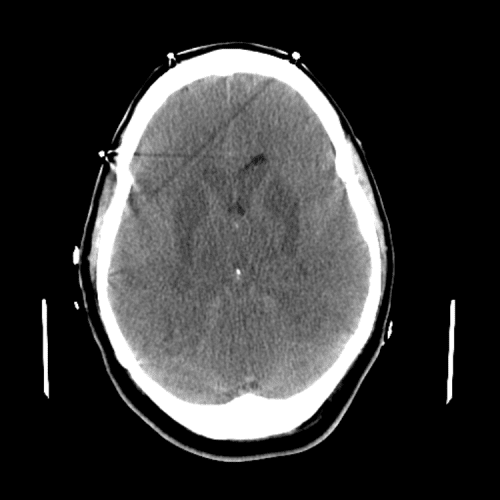

ACA and MCA territory infarct